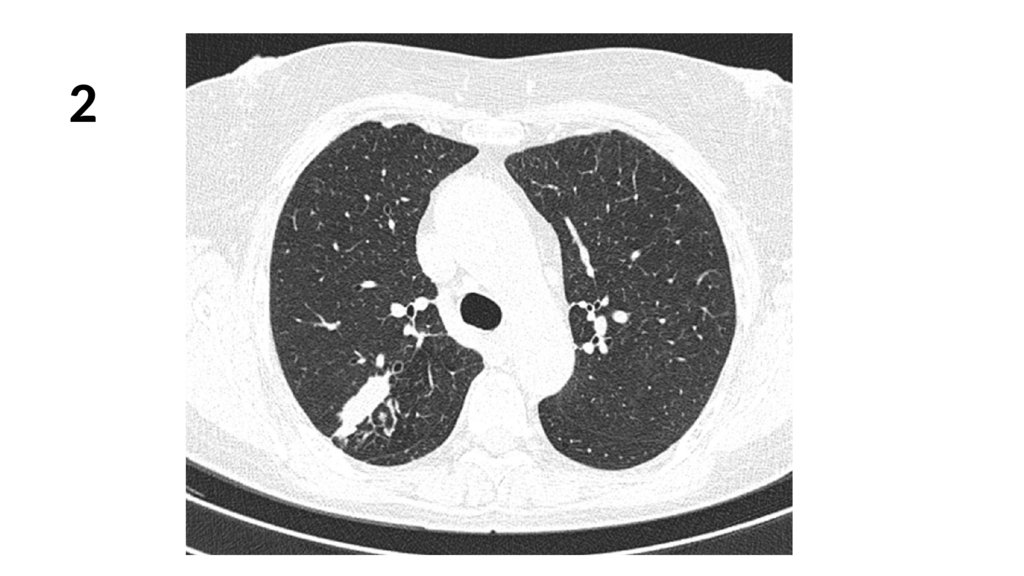

2.

1